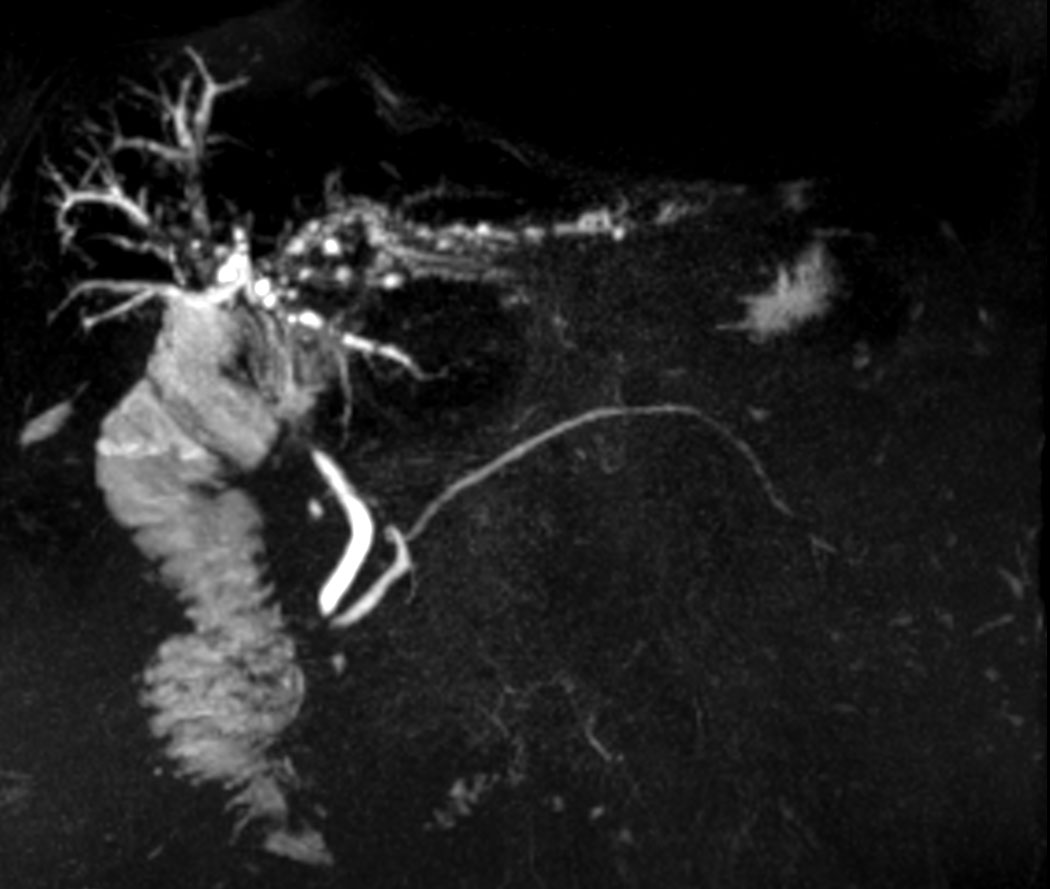

MRCP SSh - 15 radial slices

Coronal MRCP 3D

Coronal MRCP 3D - Compressed SENSE